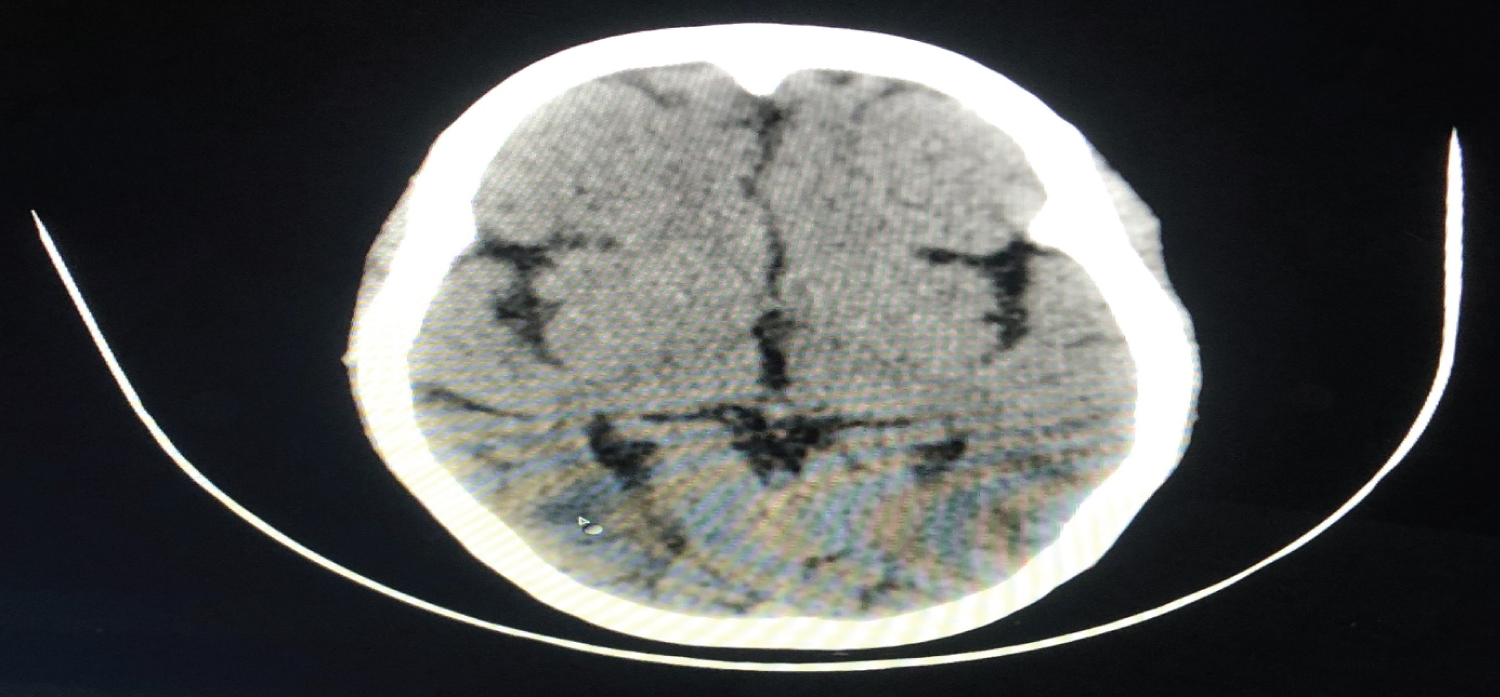

The first patient, a 20-year-old woman who underwent a caesarean section under spinal anaesthesia complained of a headache immediately after surgery and experienced a generalised tonic-clonic seizure 4 hours later. Vitals remained stable. Supplemental oxygen, midazolam, magnesium sulphate, levetiracetam, mannitol, furosemide, and steroids were used to treat the patient. The results of a brain MRI showed subcortical vasogenic edoema suggestive with PRES and bilaterally symmetrical areas of altered signal intensity in the fronto-parieto-occipital and right basal ganglia. Within 4 days, the patient had improved (Figure 1 and Figure 2).

Figure 1: MRI Brain depicting areas of altered signal intensity in right basal ganglia region. View Figure 1

Another patient with a history of postpartum generalised tonic-clonic seizures was admitted to the emergency department. Patient was unconscious, with a pulse rate of 105 beats per minute, a blood pressure of 190/110 mmHg, and a GCS of 7/15. There was no prior history of pregnancy-related hypertension or epilepsy. The patient was managed with magnesium sulphate, levetiracetam, mannitol, furosemide, steroids and was started on nitroglycerin infusion for 24 hours while still on ventilator support. Thereafter, labetalol infusion was administered. The NCCT brain revealed bilateral parieto-occipital cortical and subcortical regions with symmetrical hypodense areas, which is suggestive of PRES. Patient spent 10 days in ICU without any incidence of seizures before being transferred to the ward (Figure 3).

Figure 3: NCCT head showing symmetrical hypodense areas involving cortical and subcortical region of bilateral parieto-occipital region. View Figure 3